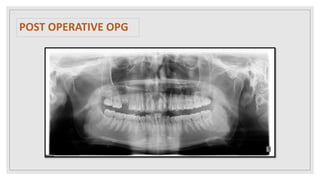

POST OPERATIVE OPG

FINAL DIAGNOSIS  Dentigerouscyst irt 11,21 POST OPERATIVE FOLLOW UP 1 WEEK FOLLOWUP 1 MONTH FOLLOWUP

• #23 Healing is satisfactory and no recurrence of lesion